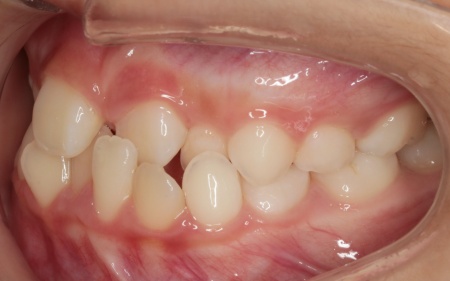

10歳女の子 顎の幅を広げる装置とマウスピース型の矯正装置で反対咬合を改善した症例

拝見したところ、上前歯が下前歯の内側に入り込む「反対咬合(こうごう)」が認められました。

詳しい検査の結果、患者様の反対咬合は歯の位置の問題ではなく、上顎の発育が十分ではないことが主な原因と考えられます。

まずは、バイオブロックを用いて上顎の拡大を行います。

慎重に調整を重ねながら、顎を適切な幅まで拡大するとともに、噛み合わせの変化を細かく確認して治療を進めました。